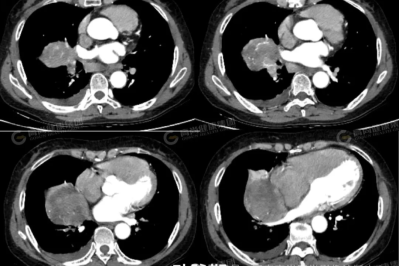

【高尚病例】巨大硬化性肺细胞瘤 1 例